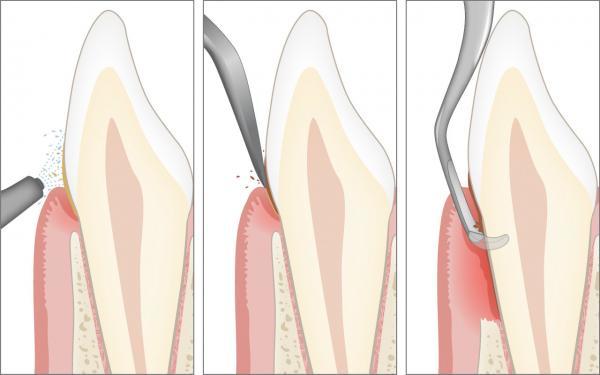

Therapie der Parodontitis

Die professionelle Zahnreinigung in der Zahnarztpraxis ist der entscheidende erste Schritt der Therapie einer Parodontitis. Ebenso wichtig sind das Anpassen der optimalen häuslichen Mundhygiene und die regelmässigen Nachsorgetermine bei der Dentalhygienikerin.